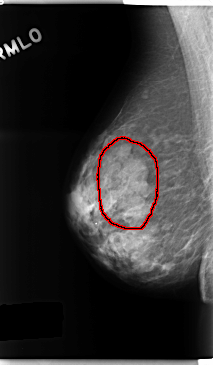

FILE: C_0247_1.LEFT_MLO.OVERLAY

TOTAL_ABNORMALITIES 2

ABNORMALITY 1

LESION_TYPE MASS SHAPE OVAL MARGINS CIRCUMSCRIBED

ASSESSMENT 3

SUBTLETY 5

PATHOLOGY BENIGN

TOTAL_OUTLINES 1

BOUNDARY

ABNORMALITY 2

LESION_TYPE CALCIFICATION TYPE AMORPHOUS DISTRIBUTION CLUSTERED

ASSESSMENT 4

SUBTLETY 3